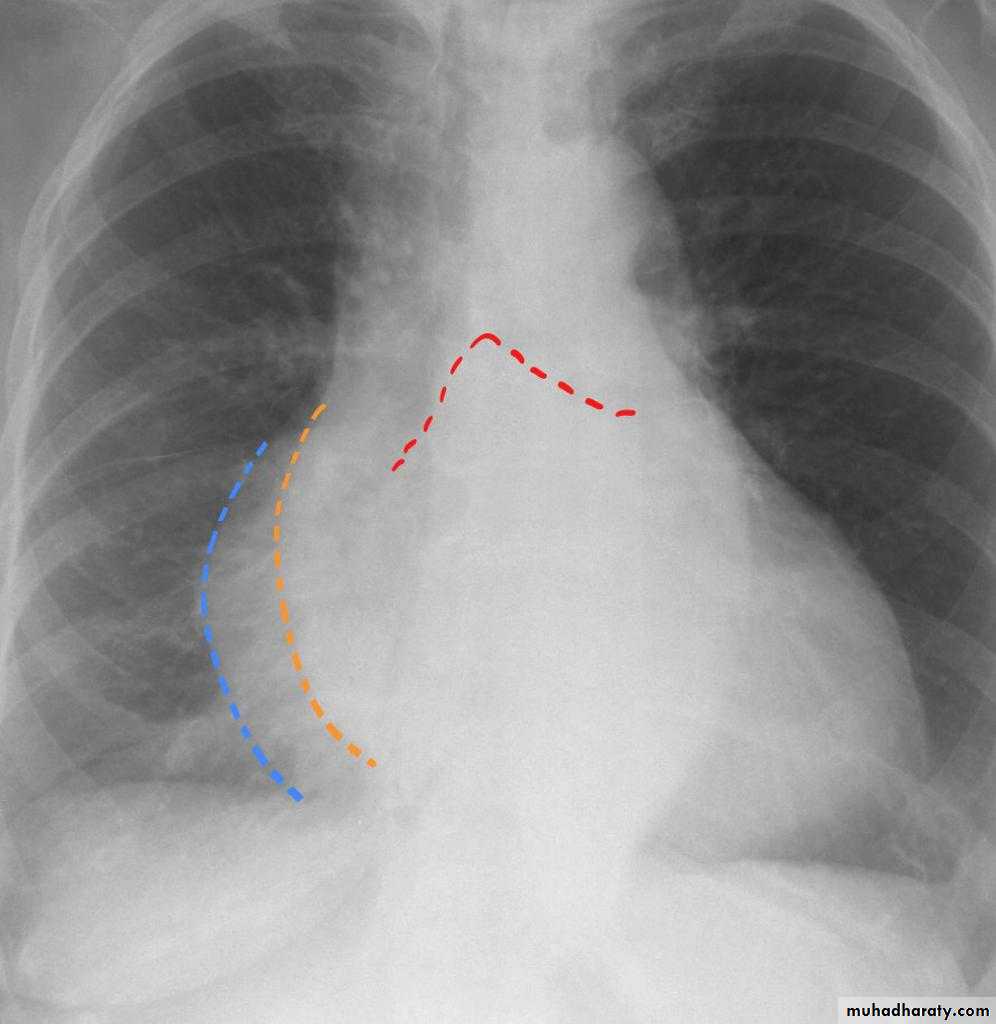

Cardiothoracic ratio (CTR) = Cardiac Width : Thoracic Width

A CTR of greater than 1:2 (50%) is considered abnormal. This however, assumes the projection is Posterior-Anterior (PA), and that cardiac size is not exaggerated by factors such as patient rotation or an incomplete breath in .

The cardiothoracic ratio aids in the detection of cardiomegaly, or more broadly, HYPERLINK "http://radiopaedia.org/articles/enlargement-of-the-cardiac-silhouette" enlargement of the cardiac silhouette.

Enlargement of the cardiac silhouette on chest x-ray can be due to a number of causes :

cardiomegaly (most common cause by far)pericardial effusion